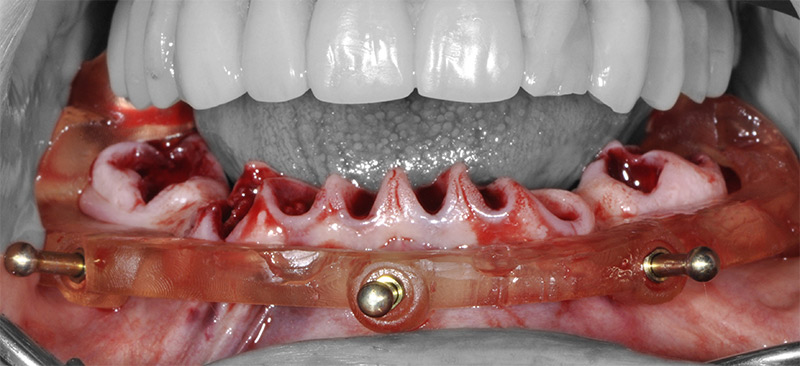

Fig. 53 : vissage des piliers prothétiques dans les implants.

Fig. 54 : transvissage des gaines temporaires sur les piliers.

Les piliers prothétiques sont immédiatement vissés dans les implants sans déposer le guide de résection osseuse ; des gaines temporaires en titane sont transvissées sur les piliers et la restauration transitoire empilée sur le guide de résection, pour être solidarisée en bouche avec une colle composite. La finition très simple est réalisée au fauteuil et le patient quitte le cabinet dès la fin de la chirurgie avec sa restauration provisoire.

Fig. 55 et 56 : restauration provisoire terminée.